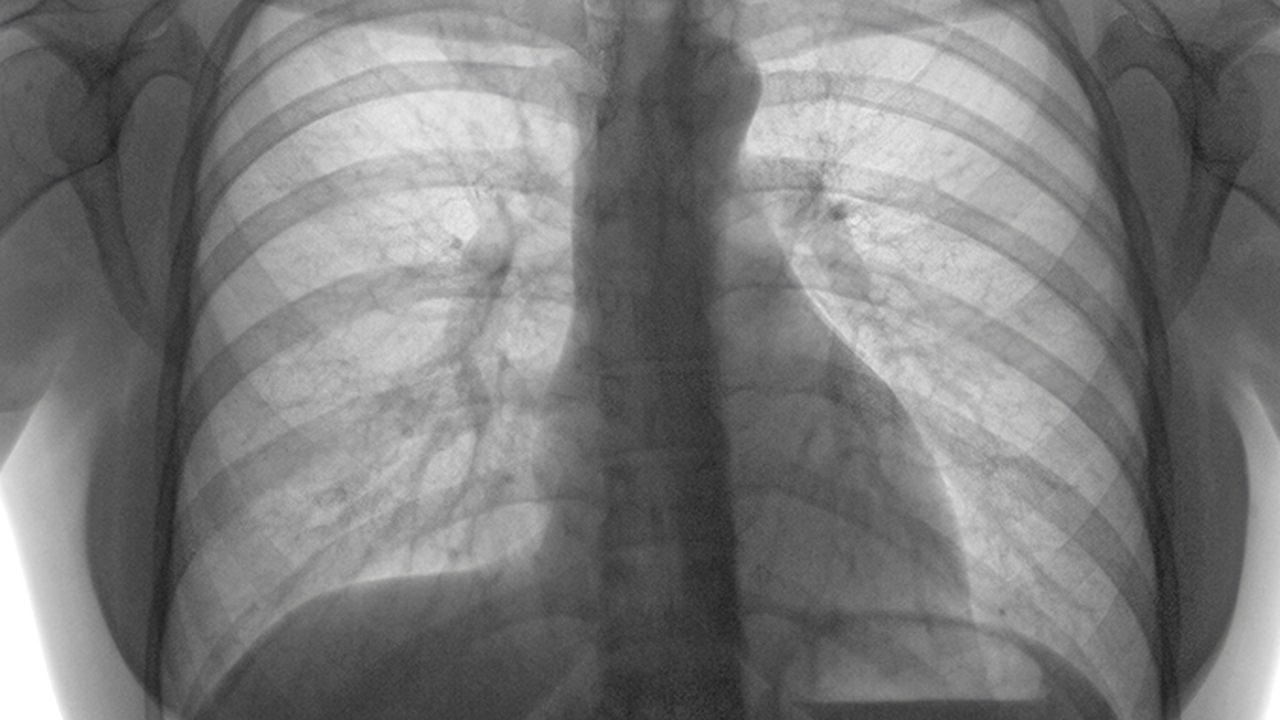

肺癌是一种常见的恶性肿瘤,其发病原因复杂,包括吸烟、环境污染、职业暴露、遗传因素等。早期诊断和规范治疗对提高患者生存率至关重要。